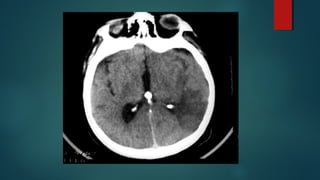

Este documento es el programa para un taller de imágenes del curso de emergencia 2015 impartido por el Dr. Víctor Delgado. El taller se centra en el uso de imágenes médicas para el diagnóstico y tratamiento de pacientes en coma traumático según la base de datos de Marshall. El Dr. Delgado es el único instructor repetido a lo largo del documento.